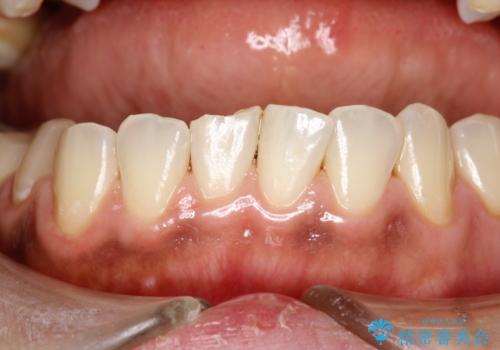

- 現在妊娠5か月で、安定期に入ったため、出産前にお口のクリーニング希望とのことでした。PMTC60分コースを行いました。

個人差がありますが、 つわりがなく妊娠前とかわらずに過ごしている方でしたら初期でもお口の中のクリーニングする事は可能です。

妊娠初期は、つわりなどの影響でしっかり磨くことができず、妊娠性歯肉炎や妊娠性歯周炎を起こしやすくなることがあります。

セルフケアだけでは、歯周病を治したり予防したりすることは困難です。

歯科医院で専門的なにクリーニングを行い、歯石除去や細菌に汚染された歯根面の掃除が大切です。